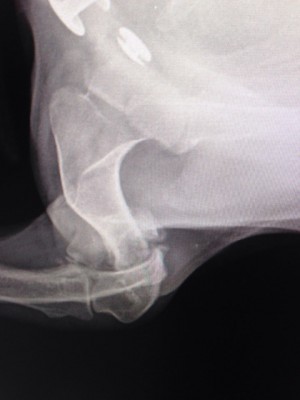

Надо мелкой рентген срочно делать

На лапу не наступает.... гипс не помню сколько был, но возможно, не правильно сложили

Вобщем все гораздо хуже оказалось.Только характер приятный,ласкавая.

Очень паршивый перелом.... сложная операция.

Не понятно куда и зачем одевали гипс.... зато стерилизовали.